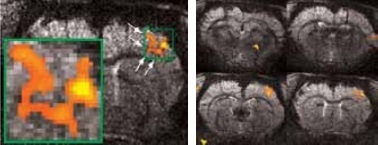

Figure 3. High resolution BOLD activation at 11.7 Tesla using the four-element array coil with a resolution of 75 x 75 x 1000 μm3 for detection of (left) sub-structures within S1, and activation within other regions along the neuronal pathway: S2 and thalamus. Image Credit: Bruker BioSpin Group

Matrices up to 256 x 256 were obtained with a four-element array coil, resulting in 75 x 75 x 1000 μm3 resolution. The activation becomes more resolved at this high resolution and allows the detection of sub-structures and shape in thalamus areas S1 and S2, as shown in Figure 3.